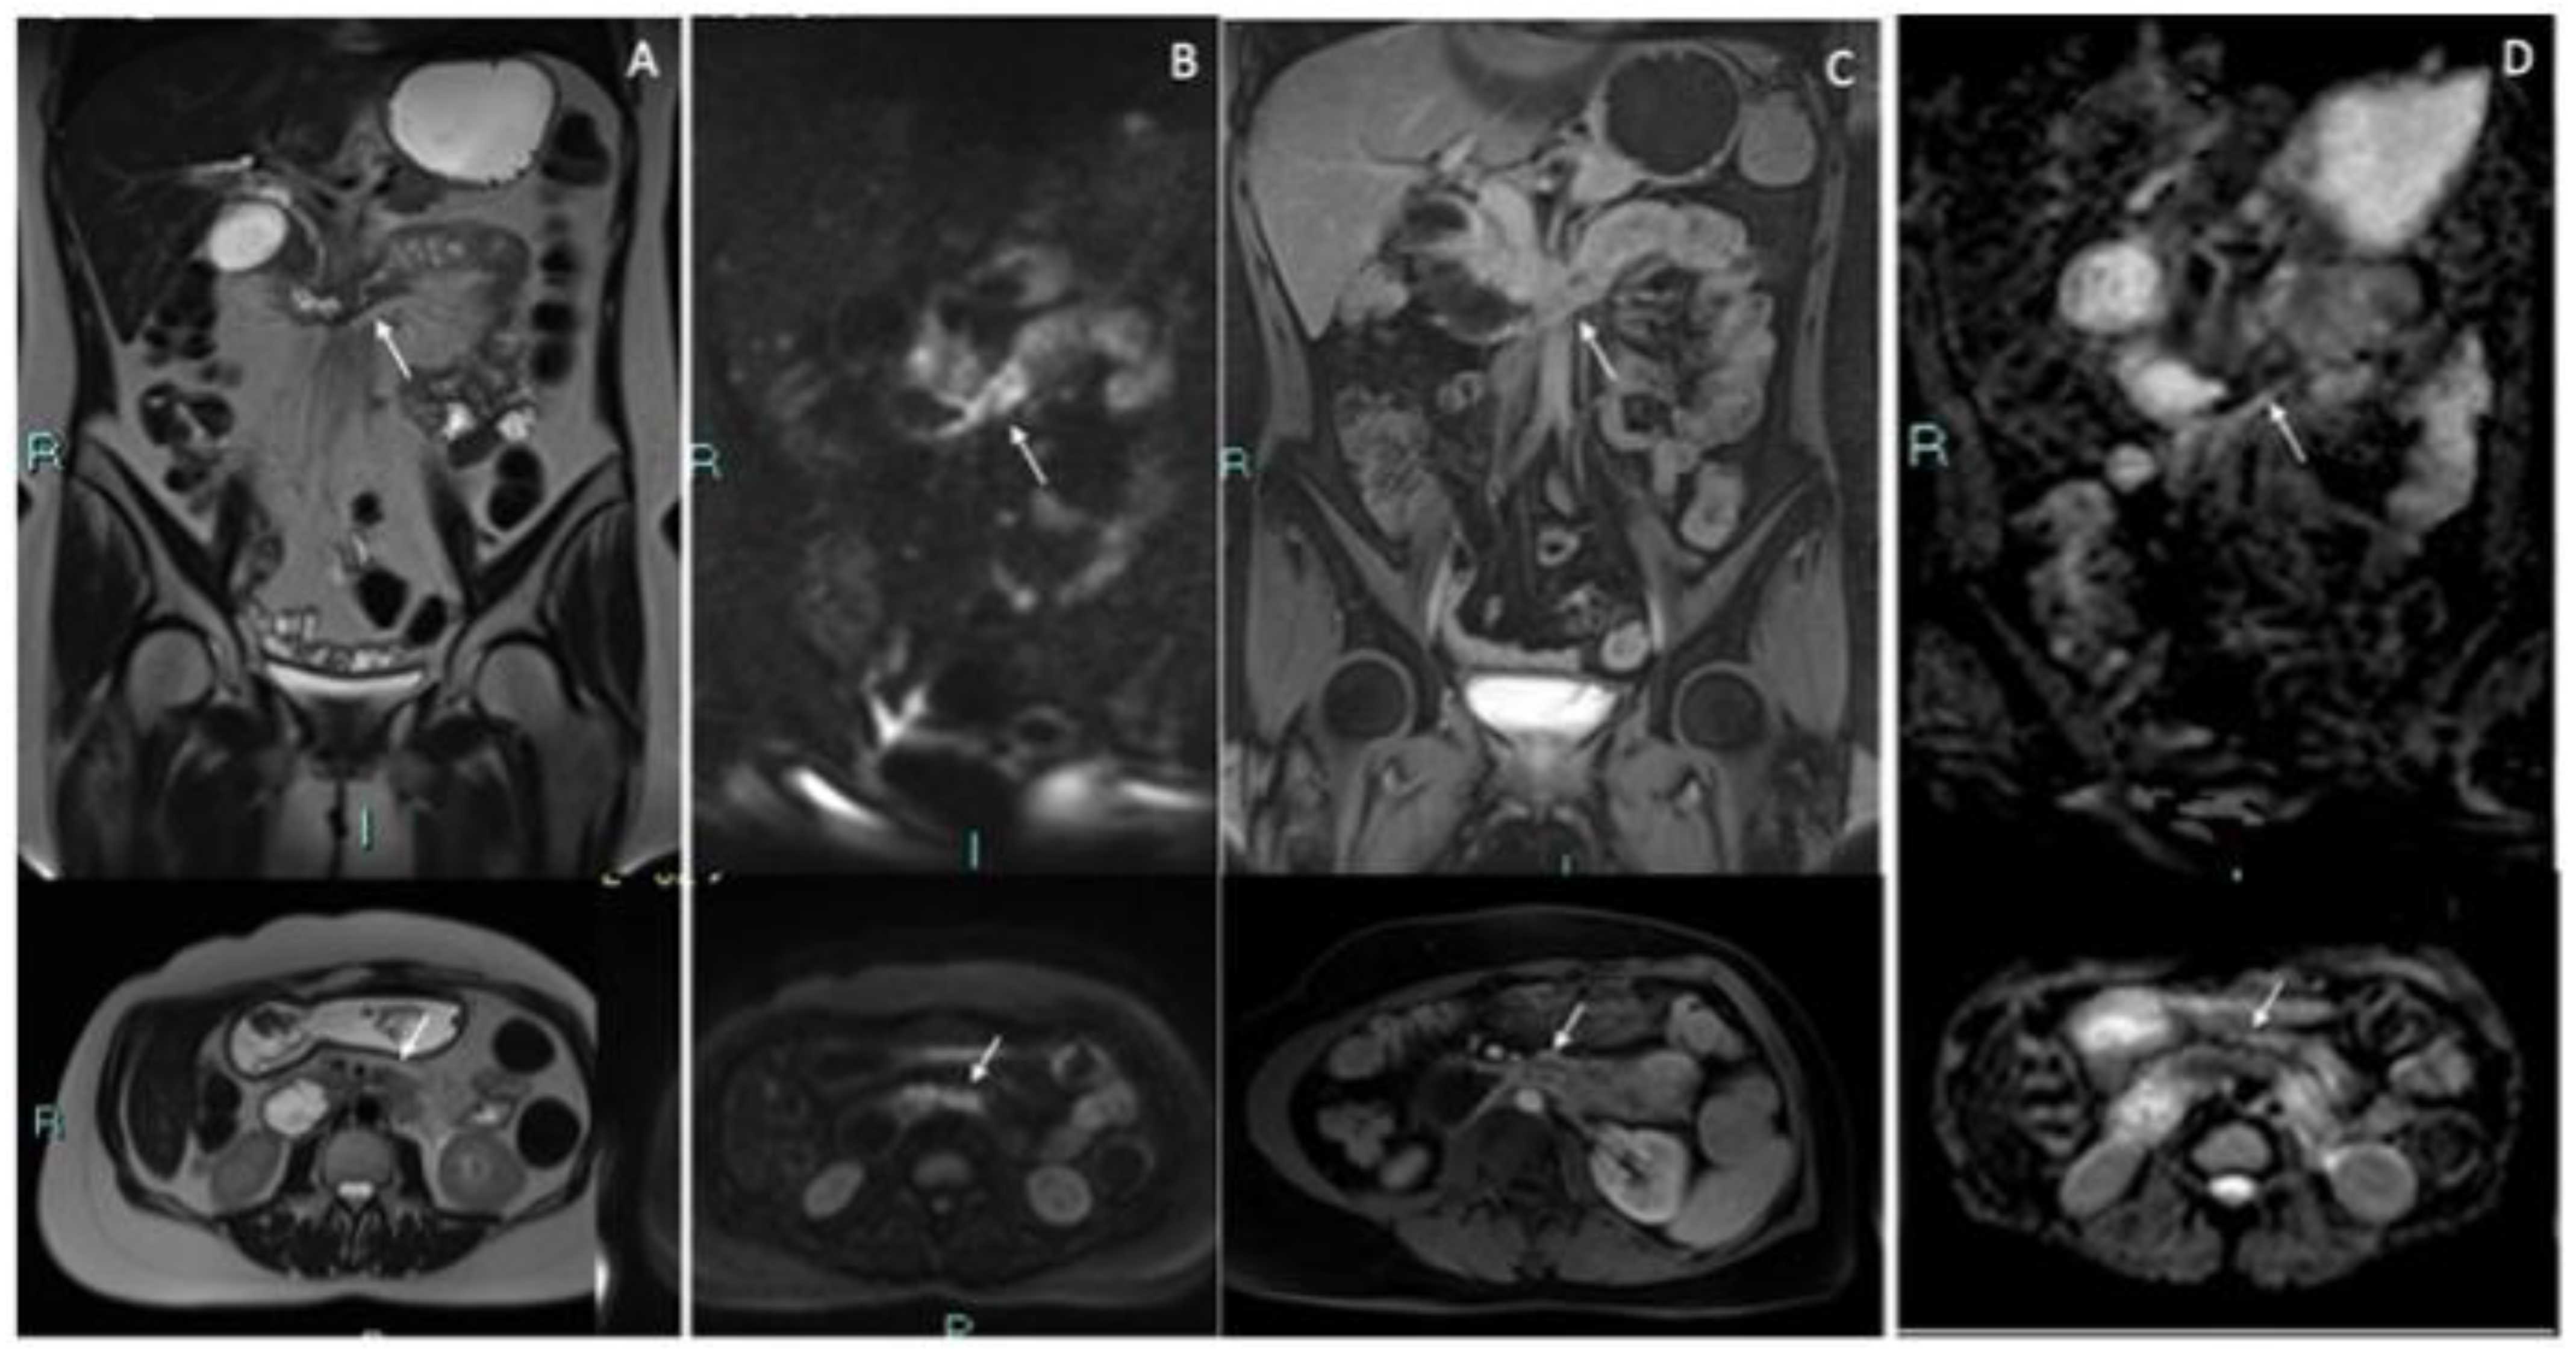

2. Case Discussion